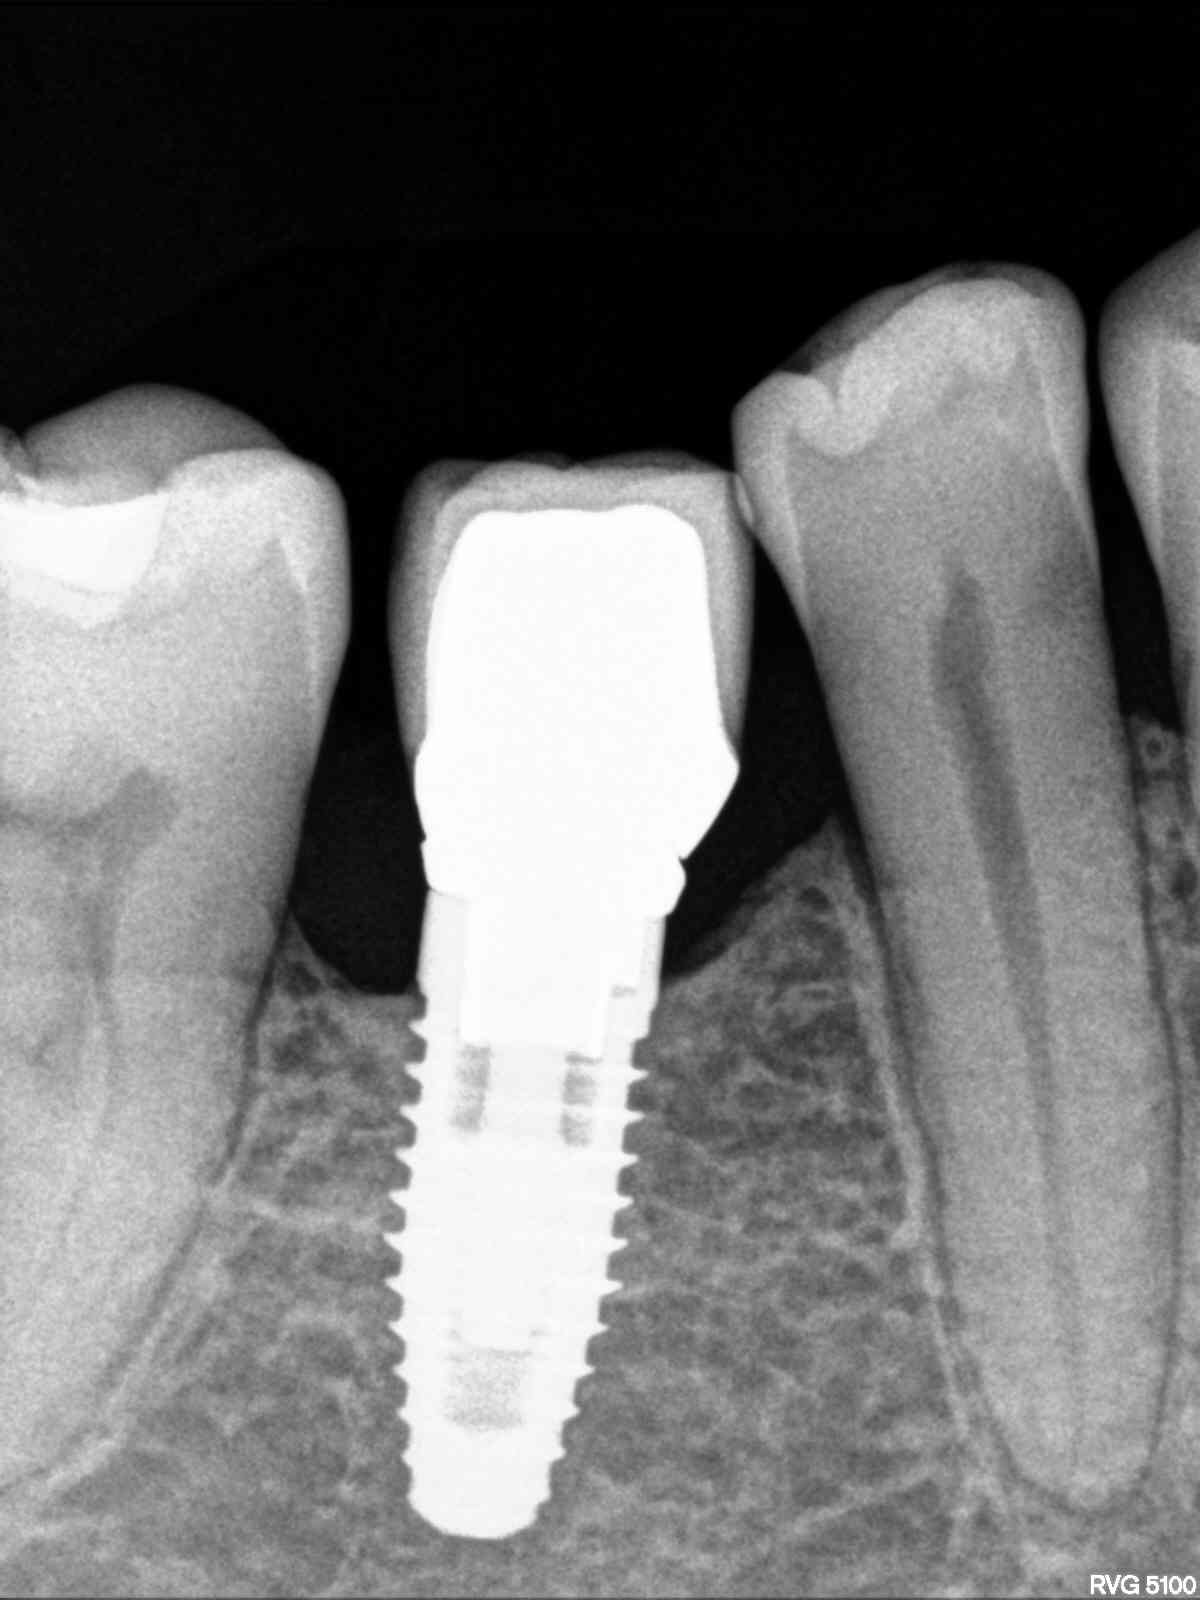

Buenos días. Soy Rubén de Reiner Dental. Una Dra. Me manda este caso referido y no ha sabido darme más información. Yo creo que es un Bramemark Podéis echarme una [...]

El paciente viene de otra clínica y quiere ponerse la corona conmigo. No sabe que marca de implante es y viene con el tapón de cicatrización. Necesito saber qué marca [...]

Buenas,¿ alguien sabe que implante es el 25? Seria para cargárselo. Gracias